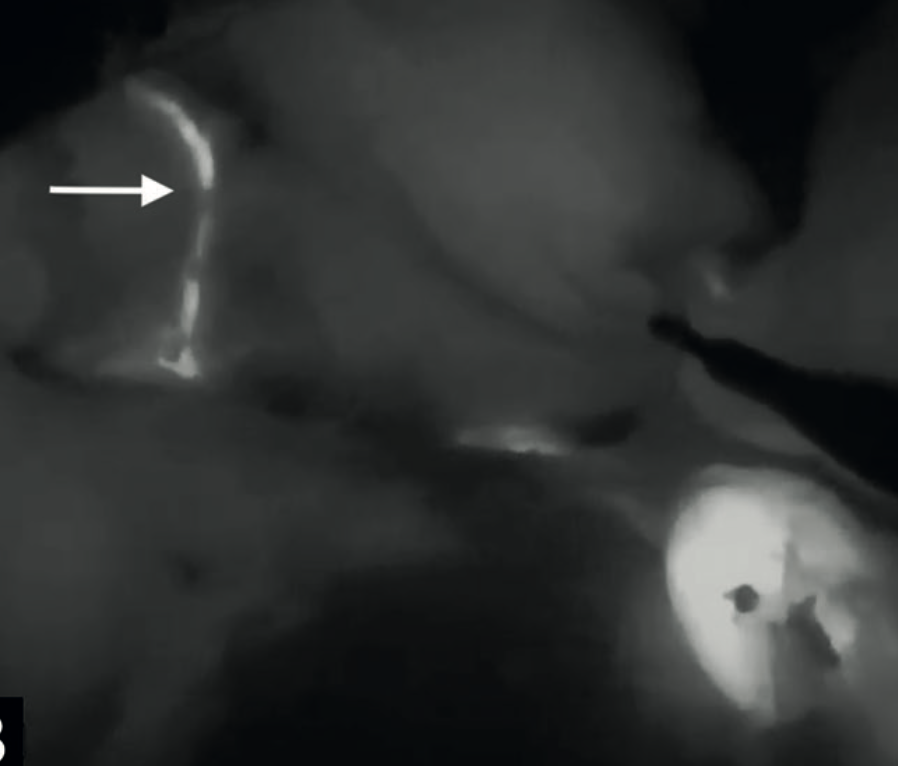

Diego Soto V, Melissa Pavez K, Sebastián Morales Z.

|